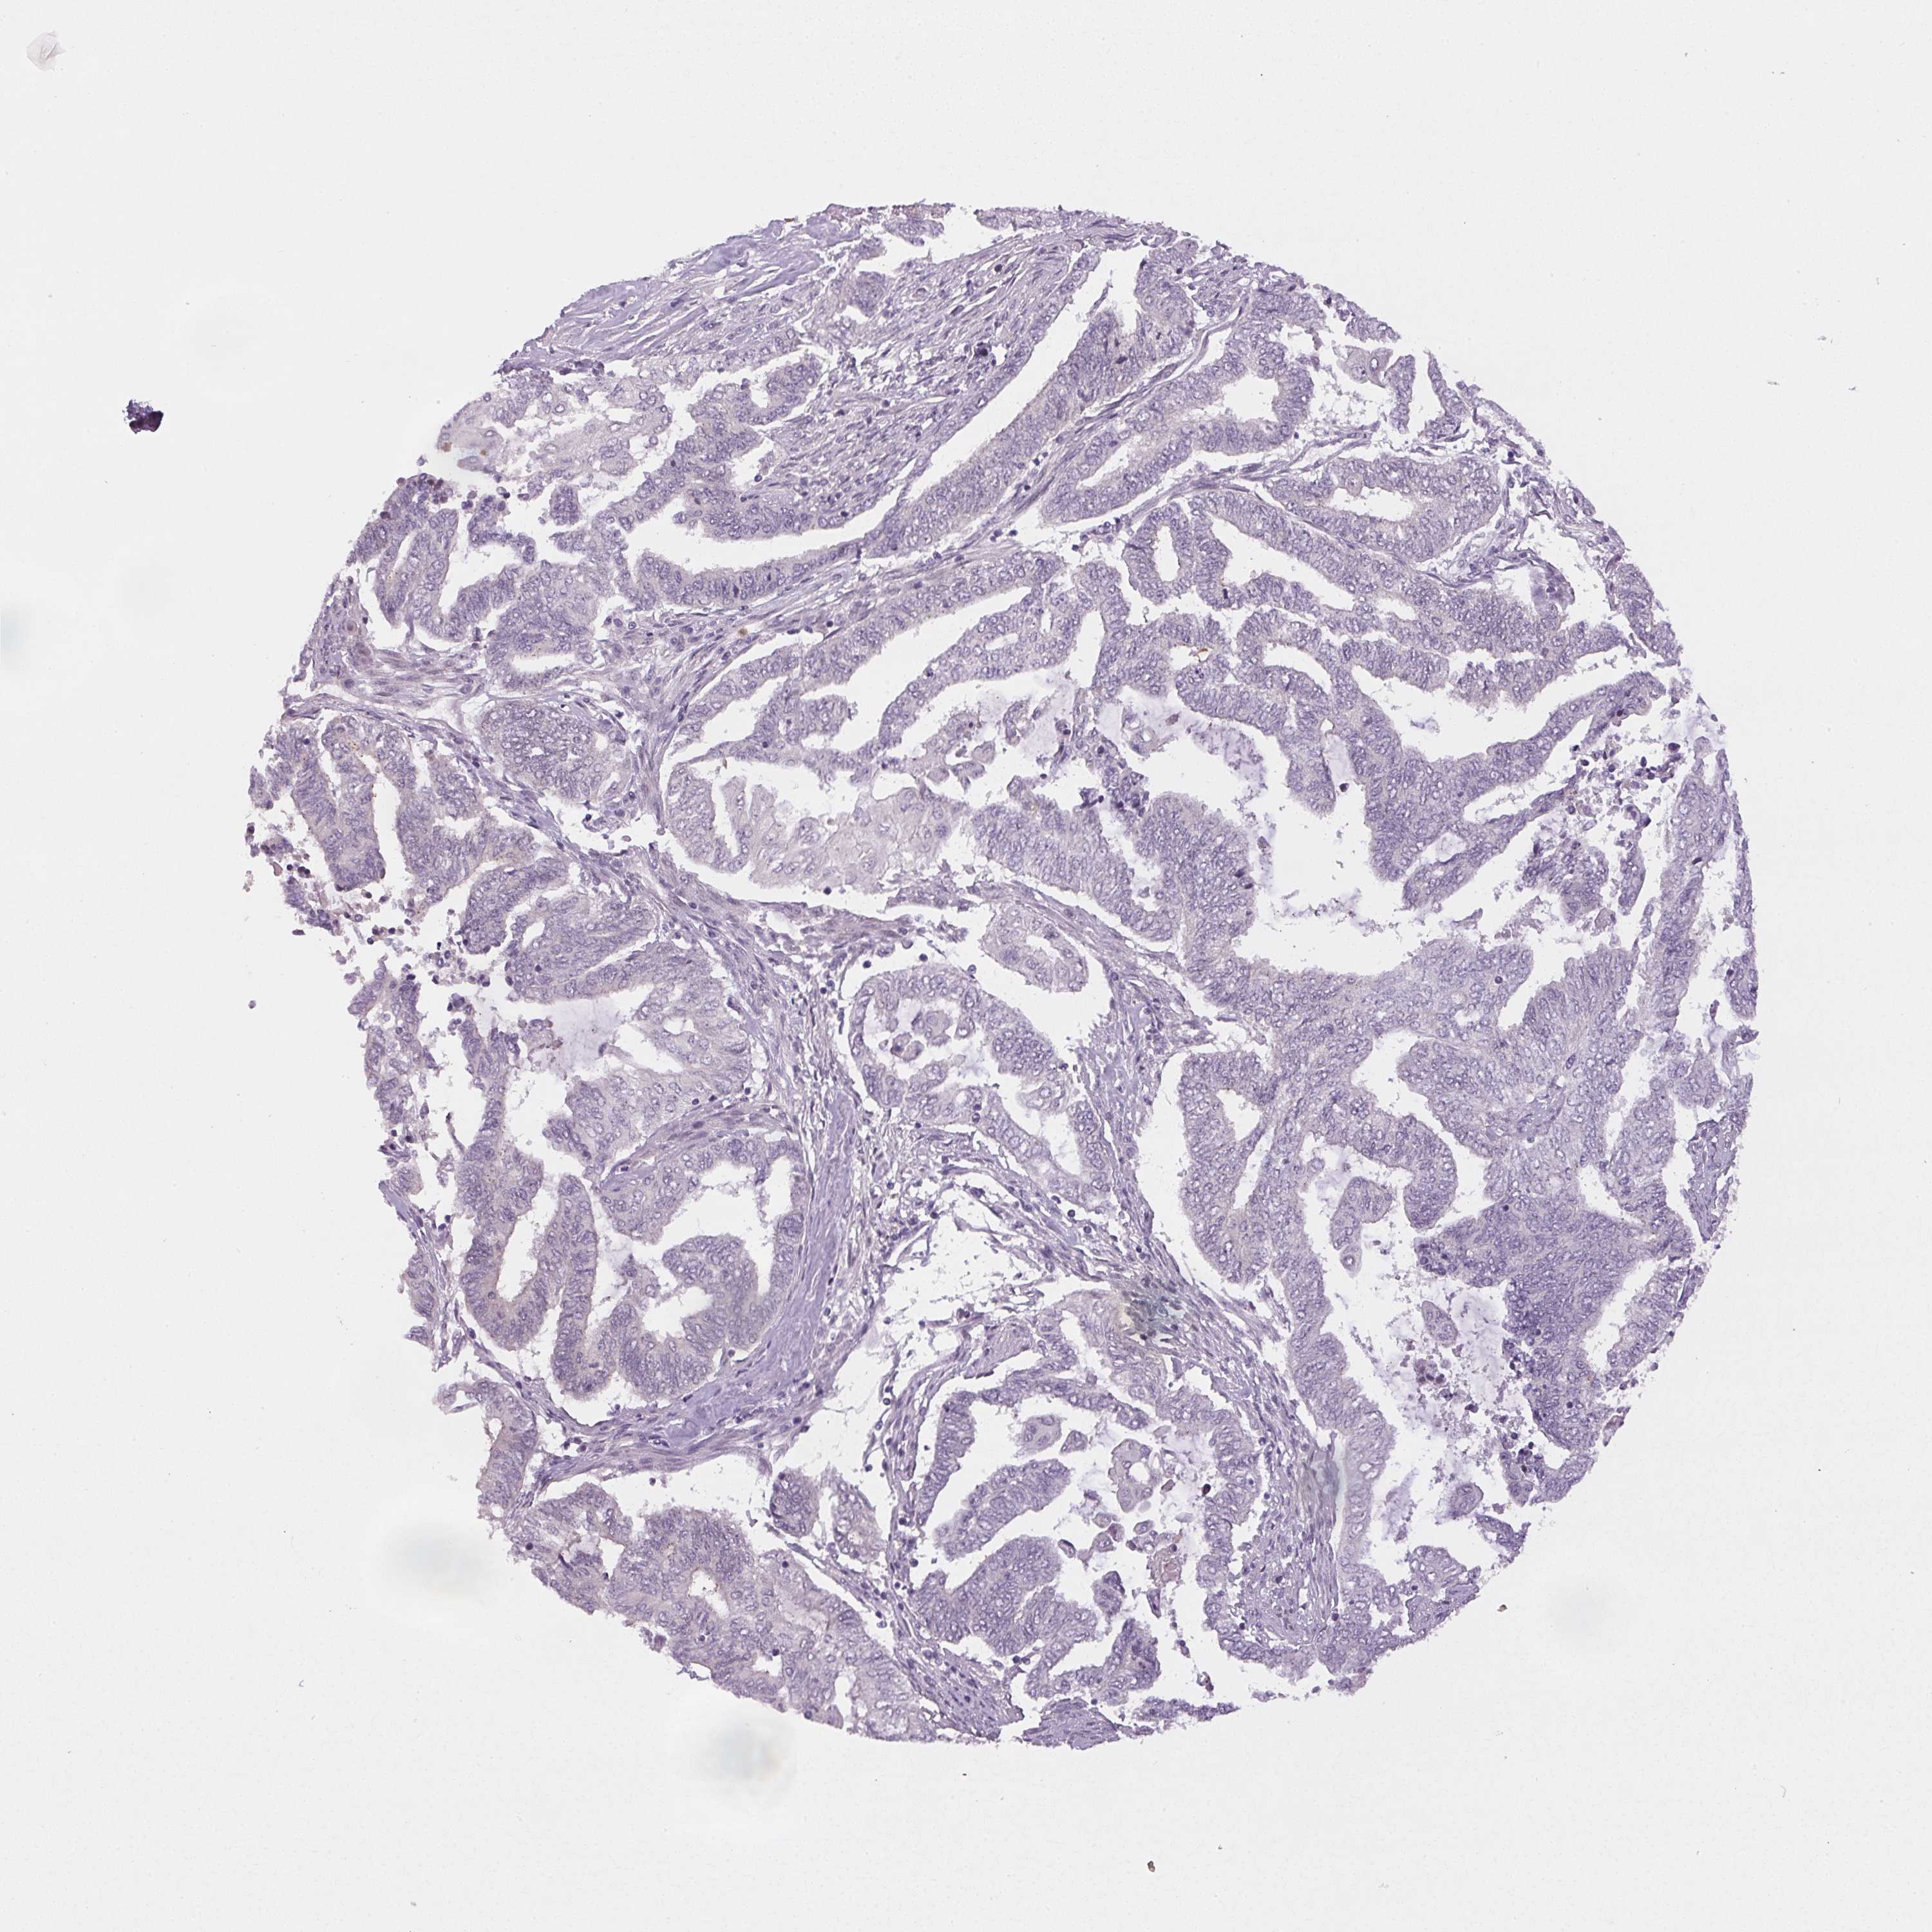

ENDOMETRIAL CANCER - Protein expressioni

A mouse-over function shows sample information and annotation data. Click on an image to view it in a full screen mode. Samples can be filtered based on level of antibody staining by selecting one or several of the following categories: high, medium, low and not detected. The assay and annotation is described here.

Note that samples used for immunohistochemistry by the Human Protein Atlas do not correspond to samples in the TCGA dataset.

Antibody stainingi

Antibody staining in the annotated cell types in the current human tissue is reported as not detected, low, medium, or high, based on conventional immunohistochemistry profiling in selected tissues. This score is based on the combination of the staining intensity and fraction of stained cells.

Each image is clickable and will lead to virtual microscopy that enables deeper exploration of all samples and also displays staining intensity scores, fraction scores and subcellular localization as well as patient and tissue information for each sample.

Antibody HPA052590

Antibody HPA053608

Staining

High

Medium

Low

Not detected

Intensity

Strong

Moderate

Weak

Negative

Quantity

>75%

75%-25%

<25%

None

Location

Nuclear

Cytoplasmic/membranous

Cytoplasmic/membranous,nuclear

Adenocarcinoma, metastatic, NOS